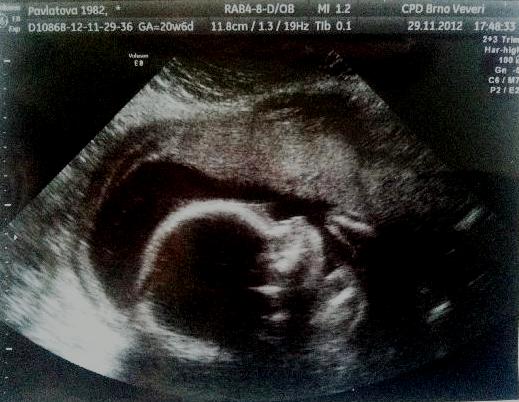

Holky děkuju já se strašne bala, alejak mi pak ukazala mimi jak povyrostlo a srdicko bylo slyset to byla nadhera ja jdu zase 13.12.